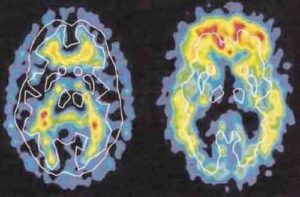

alzheimer

Un basso livello di testosterone e’ legato all’insorgenza dell’Alzheimer. Lo ha dimostrato uno studio condotto dall’universita’ di Hong Kong, che suggerisce che questo ormone potrebbe un giorno essere usato per combattere la malattia. I ricercatori hanno studiato 153 cinesi di almeno 55 anni non affetti dalla patologia, di cui 47 avevano leggeri problemi cognitivi e piccole perdite di memoria.

Dopo un anno, 10 di questi hanno sviluppato l’Alzheimer, e dalle analisi del sangue e’ risultato un basso livello di testosterone, un elevato livello della proteina ‘ApoE 4′, legata alla malattia, e un’alta pressione. “E’ un risultato importante, perche’ mostra che il livello di testosterone e’ uno dei fattori di rischio – ha commentato John Morley dell’Universita’ di Saint Louis, che ha partecipato allo studio pubblicato dal Journal of Alzheimer’s Disease – il prossimo passo sara’ studiare su larga scala l’uso del testosterone per prevenire l’insorgenza della malattia”.